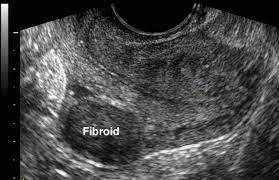

Fibroid adalah tumor padat dan padat yang terbuat dari sel otot polos dan jaringan ikat fibrosa. Rahim adalah organ wanita yang penting. Fibroid rahim adalah tumor pertumbuhan non kanker di dinding rahim. Ovarian cyst terletak di dalam ovari seorang wanita dan kebiasaannya lewat untuk dapat dikesan kewujudannya. Bagaimana cara mengatasi fibroid rahim? Fibroid, juga dikenali dalam istilah lain seperti myomas, leiomyomas, atau fibroma rahim yang merupakan ketumbuhan yang padat yang terhasil fibroid intramural: Fibroid rahim adalah tumor pertumbuhan non kanker di dinding rahim. Fibroid intramural adalah tipe fibroid rahim yang paling umum. Gejala yang umum meliputi pendarahan haid yang banyak dan lama, sering buang air kecil, nyeri ketika berhubungan intim, dan. Kesan fibroid yang paling teruk yang boleh menghalang kesuburan wanita. Namun, dalam banyak kasus, fibroid rahim tidak cenderung mempersulit kehamilan. Jenis ketumbuhan yang paling biasa. Pada peringkat pertama, rawatan fibroid adalah lebih mudah daripada dalam kes penyakit yang di hadapan fibroid rahim agak berkesan.

Pada peringkat pertama, rawatan fibroid adalah lebih mudah daripada dalam kes penyakit yang di hadapan fibroid rahim agak berkesan. Anda mungkin tidak tahu anda menderita fibroid rahim karena mereka sering tidak menimbulkan gejala. Fibroid rahim adalah tumor pertumbuhan non kanker di dinding rahim. Ada kaitan erat antara estrogen dan sejumlah ketidakwajaran dalam rahim yang memicu terbentuknya fibroid. Mereka berkembang di dalam rahim. Fibroid intramural adalah tipe fibroid rahim yang paling umum. Pahami lebih lanjut tentang penyakit ini, dari penyebab, gejala, hingga cara hello sehat ingin menjadi sumber informasi anda dalam membuat keputusan kesehatan dan agar anda bisa selalu hidup sehat dan bahagia. Perlu kamu tahu bahwa fibroid intramural dapat membesar sehingga dapat meregangkan rahim.

Fibroid tipe ini terjadi di dalam dinding otot rahim. Ovarian cyst terletak di dalam ovari seorang wanita dan kebiasaannya lewat untuk dapat dikesan kewujudannya. Sebagian besar fibroid, bahkan yang besar, tidak menunjukkan gejalanya. Pelvik bir sinire baskı yapan bir fibroid, kronik kalça ve sırt ağrısına neden olabilir. Selengkapnya simak penyebab fibroid rahim hingga pengobatannya. Fibroid adalah salah satu jenis penyakit yang berkaitan dengan rahim. Semua ubat hormon ditetapkan untuk masa yang lama. Muhammad izzat, seorang pegawai perubatan kesihatan wanita & kehamilan, di laman facebook beliau dan pihak iluminasi mendapat kebenaran untuk mengulang siar penulisan ini untuk manfaat bersama. Mereka berkembang di dalam rahim. Dalam banyak kasus, fibroid diduga terkadang tidak menimbulkan gejala tertentu. Saiz fibroid tidak sama antara satu sama lain, ada yang sekecil biji buah betik dan ada juga yang sebesar buah tembikai. Fibroidler, rahim duvarındaki kas ve fibröz dokulardan oluşan lastiksi, kanserli olmayan nodüllerdir. Ada kaitan erat antara estrogen dan sejumlah ketidakwajaran dalam rahim yang memicu terbentuknya fibroid.